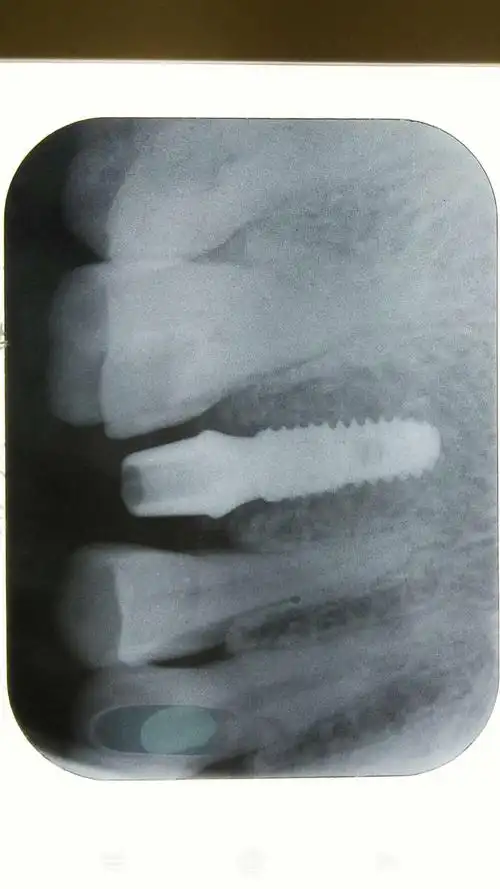

即拔即种植牙实例 请点我

种牙牙片欣赏

我的种植牙日记机械维修工程师的渡江口腔种植修复之路